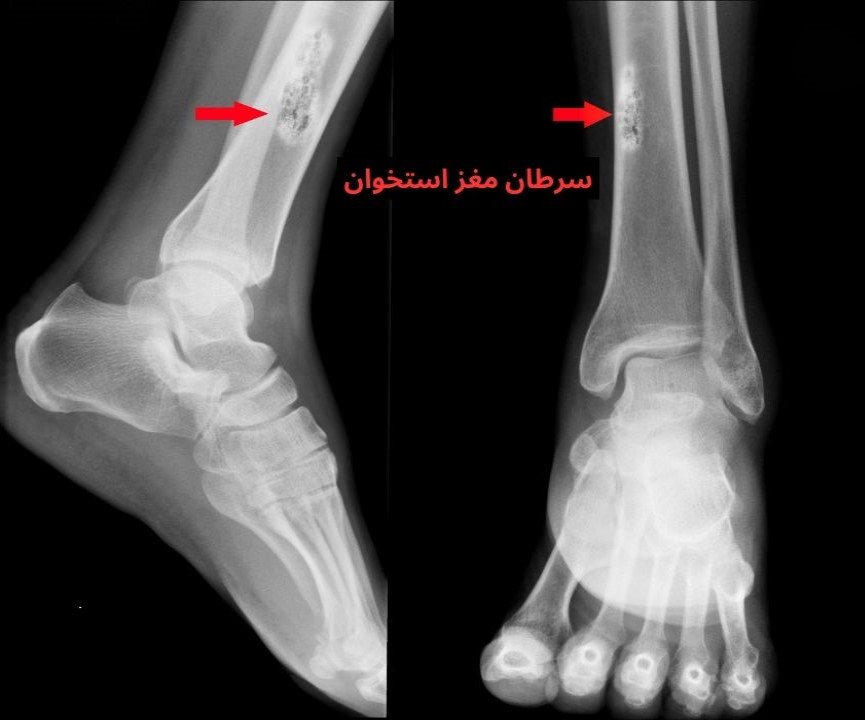

مغز استخوان در مرکز استخوانها قرار دارد. در اصل یک بافت نرم و اسفنجیشکل که در آن سلولهای بنیادی به سلولهای خونی یعنی گلبولهای قرمز، گلبولهای سفید و پلاکتها تبدیل میشوند. در اثر عوامل مختلفی، ممکن است سلولهای مغز استخوان شروع به رشد سریع و غیرقابل کنترل کنند. این وضعیت میتواند منجر به ایجاد تومور استخوان و در مرحله بعد سرطان مغز استخوان شود. گاهی نیز علت بروز سرطان در این ناحیه، گسترش سلولهای سرطانی از مناطق دیگر بدن به استخوانها است.

تشخیص سرطان مغز استخوان

اگر مدتی است که با علائم ذکر شده مواجه شدهاید، توصیه میکنیم در اولین فرصت به پزشک مراجعه کنید. پزشک برای تشخیص، ابتدا شما را معاینه میکند و سوالاتی در مورد سابقه پزشکی و خانوادگی شما میپرسد. سپس برحسب دادههای بدستآمده دستور انجام یک یا چند مورد از آزمایشهای زیر را میدهد:

- آزمایشهای تصویربرداری مانند سی تی اسکن، ام آر آی و پِت اسکن برای مشاهده نشانههای تومور در مغز استخوان و میزان گسترش سرطان